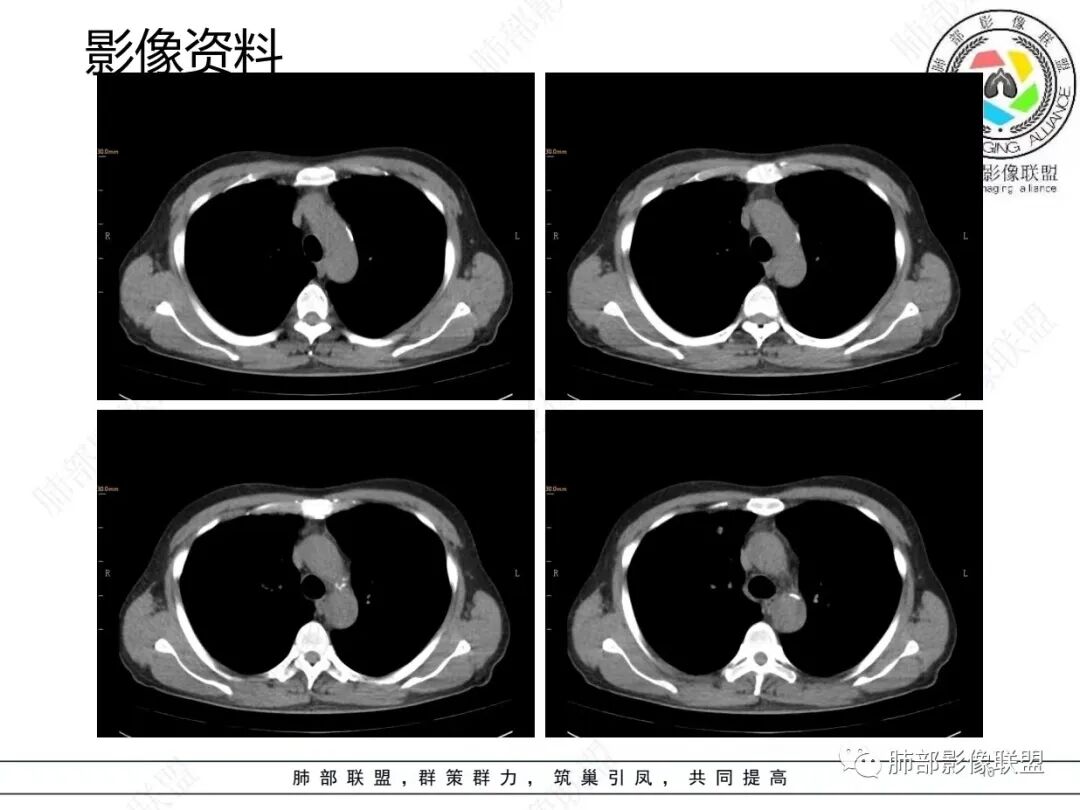

1.临床特点:52岁男性,体检发现肺结节。有吸烟史。非小细胞肺癌相关抗原与神经元烯醇化酶轻度升高。2.影像特点:右肺上叶前段可见不规则结节影,整体膨隆,可见浅分叶,周围局部可见边界清楚的磨玻璃影。可见血管集束征及脐凹征,临近叶间胸膜受牵拉凹陷,局部支气管到达病灶边缘后显示截断。3.病例小结:中老年吸烟男性,右肺上叶前段不规则结节,膨胀感较明显,收缩力强,支气管截断,加上边界清楚的磨玻璃影。符合浸润性腺癌表现。